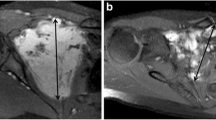

Figure 3 shows an example of the relationship between the signal and DF growth behavior.

a, b An 18-year-old female with a DF to the posterior compartment of the left knee (white stars). a Axial T2-weighted fat-saturated MR image showing a DF with a T2 ratio < 1. b T2-weighted fat-saturated axial MR image of the same patient, 80 months later, showing stable lesion volume and signal. c, d A 62-year-old male with a DF to the medial part of the left knee (white arrows). c Coronal T2-weighted fat-saturated MR image showing a DF with a T2 ratio > 1. d Coronal T2-weighted fat-saturated MR image of the same patient 17 months later showing an increase in lesion volume and signal